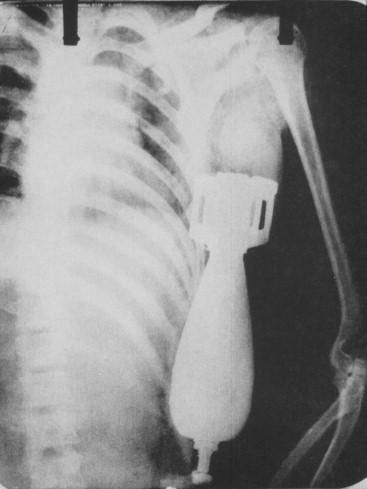

Itu adalah hasil sinar-X.

Di layar hitam putih yang berpendar itu, terlihat siluet yang tak lazim bagi anatomi manusia. Sebuah benda berbentuk torpedo kecil, bersirip, bersarang miring menembus dinding dada, berhenti tepat di bawah ketiak, menekan paru-paru.

Itu bukan pecahan peluru. Itu adalah proyektil mortir 60mm utuh. Dan sekeringnya (fuse) masih aktif.